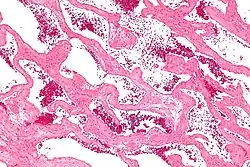

| Micrograph of a cavernous liver hemangioma. H&E stain. | |

Cavernous hemangioma, also called cavernous angioma, venous malformation, or cavernoma,[1][2] is a type of venous malformation due to endothelial dysmorphogenesis from a lesion which is present at birth. A cavernoma in the brain is called a cerebral cavernous malformation or CCM. Despite its designation as a hemangioma, a cavernous hemangioma is a benign (but not harmless) condition, not a malignant tumor, as it does not display endothelial hyperplasia. The abnormal tissue causes a slowing of blood flow through the cavities, or "caverns". The blood vessels do not form the necessary junctions with surrounding cells, and the structural support from the smooth muscle is hindered, causing leakage into the surrounding tissue. It is the leakage of blood (hemorrhage) that causes a variety of symptoms known to be associated with the condition.

Cavernous hemangiomas can arise nearly anywhere in the body where there are blood vessels. They are sometimes described as resembling raspberries because of the appearance of bubble-like caverns. Unlike capillary hemangiomas, cavernous ones can be life-threatening and do not regress.